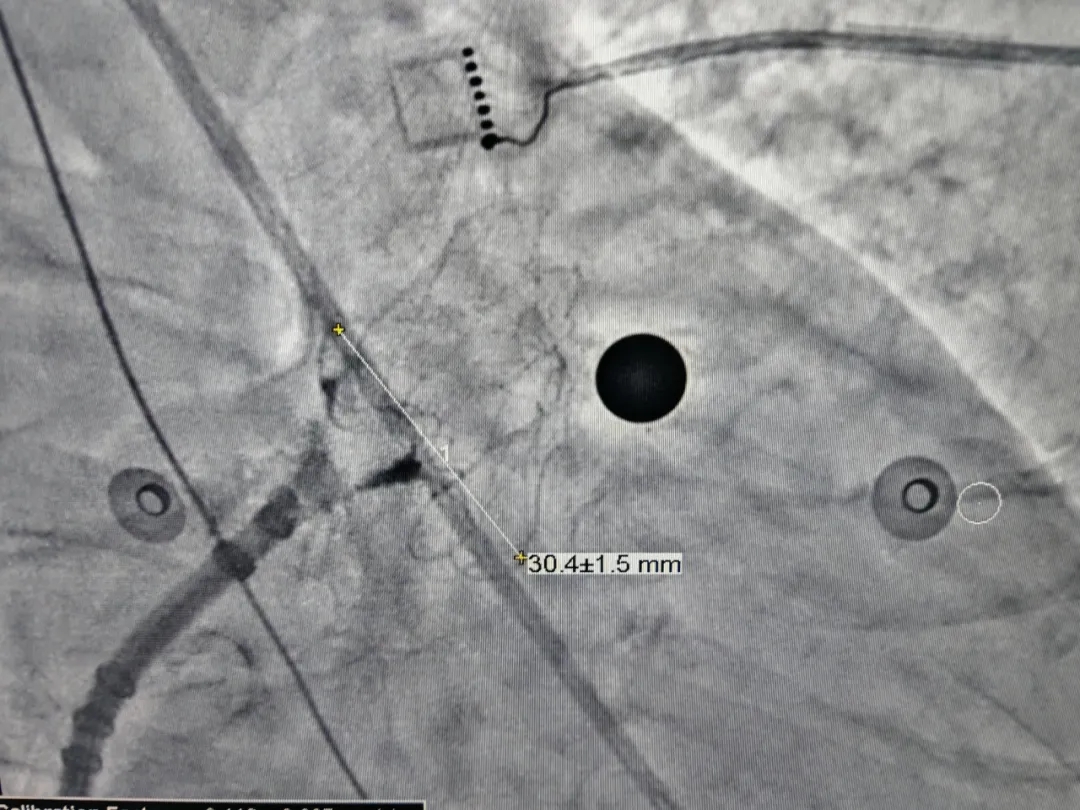

展开后DSA下充分评估

压缩比10.6%,在8%-30%之间,符合推荐压缩比

封堵器释放后造影,无残余分流

释放后造影评估

MemoLefort封堵器评估符合PASS原则,释放封堵器,释放后,封堵器完美贴合心耳口,位置稳定且未见残余漏。